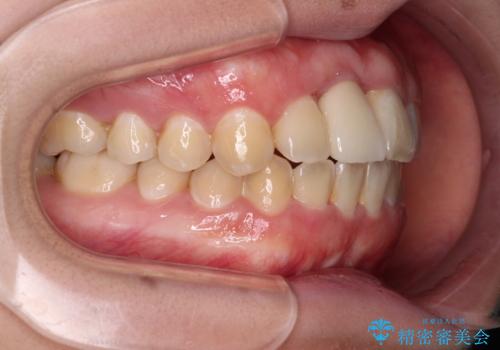

ぶつけてしまった歯は保存が困難な状況であったので抜歯をし、ワイヤー矯正により歯列を整えつつ前歯の突出感を解消することとしました。

矯正治療後にはインプラント補綴治療を行うこととしました。

前歯の補綴治療はインプラントかブリッジかで悩んでいました。

周りの歯にむし歯がないため、インプラントがお勧めとなりますが、事故による骨欠損が大きく、歯肉ラインを整えるのが困難という問題がありました。